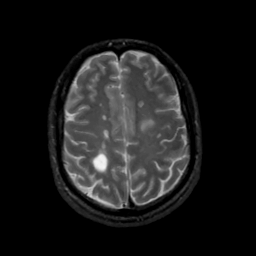

MR Study #10, April 28, 1991 -- Slice #37